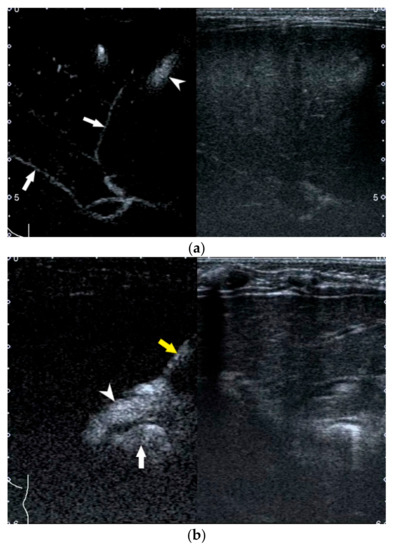

- Zhou, L.-Y.; Chen, S.-L.; Chen, H.-D.; Huang, Y.; Qiu, Y.-X.; Zhong, W.; Xie, X.-Y. Percutaneous US-guided Cholecystocholangiography with Microbubbles for Assessment of Infants with US Findings Equivocal for Biliary Atresia and Gallbladder Longer than 1.5 cm: A Pilot Study. Radiology 2018, 286, 1033–1039. [Google Scholar] [CrossRef]

- Lee, S.Y.; Kim, G.C.; Choe, B.-H.; Ryeom, H.K.; Jang, Y.-J.; Kim, H.J.; Park, J.Y.; Cho, S.-M. Efficacy of US-guided Percutaneous Cholecystocholangiography for the Early Exclusion and Type Determination of Biliary Atresia. Radiology 2011, 261, 916–922. [Google Scholar] [CrossRef] [Green Version]